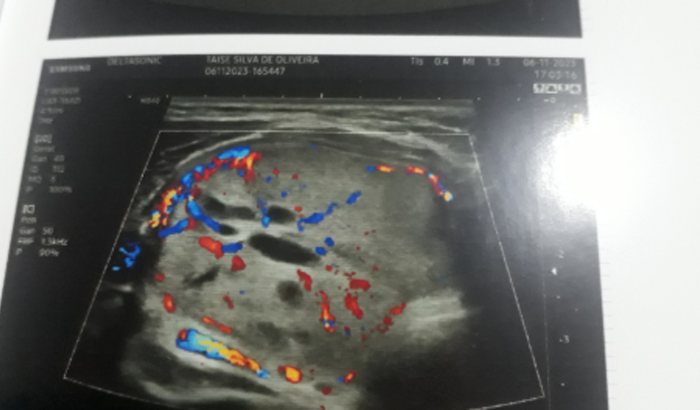

Olá, me chamo Taise Oliveira e no momento estou passando aqui para pedir a ajuda de todos que puderem ajudar, estou passando um momento delicado onde descobri dois nódulos avançados “37 mm”, malignos e outros 5 em origem ainda na região do pescoço, crescendo muito rápido, alguns na tiróide outros não como na imagem do ultrasom… Tenho cirurgia marcada para dia 14/12 as 11h no hospital Erasto Gaertner e vim pedir o apoio de vocês para me ajudar com os gastos gerais que teremos, meu esposo é a única pessoa para me ajudar no momento e não está conseguindo arcar com tudo já que recentemente fiz uma cesária e estamos com um bebê recém nascido, além dos demais, aqui eu Taise não tenho familia próxima para ajudar e são pouquissimas pessoas que consigo contar ! Se tiver interesse em ajudar pelo link da vaquinha ou pelo pix 02508003069 meu cpf “Taise S de Oliveira” peço a todos que orem e que em breve tudo esteja bem e que logo seja só uma lembrança desagradável. Muito obrigado a todos e conto com a sua ajuda.